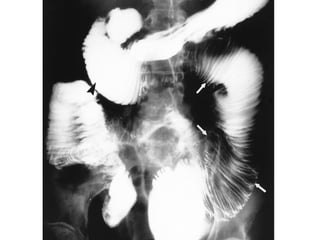

Small bowel scleroderma

Location:

• Most common duodenum.

Pathology:

Preferential atrophy of the inner circular smooth muscle layer

relative to the outer longitudinal layer

Contraction of the longitudinal layer result in foreshortening of

the bowel & packing of valvulae conniventes.

Motility disorder:

• Decreased peristalsis (fluoroscopy).

• Delayed small bowel transit time.

Radiological manifestations:

• Hidebound sign (crowding of valvulae conniventes).

• Small bowel dilatation (mega-duodenum or mega-jejenum).

Hidebound

sign

= stack of

coin sign

= accordion